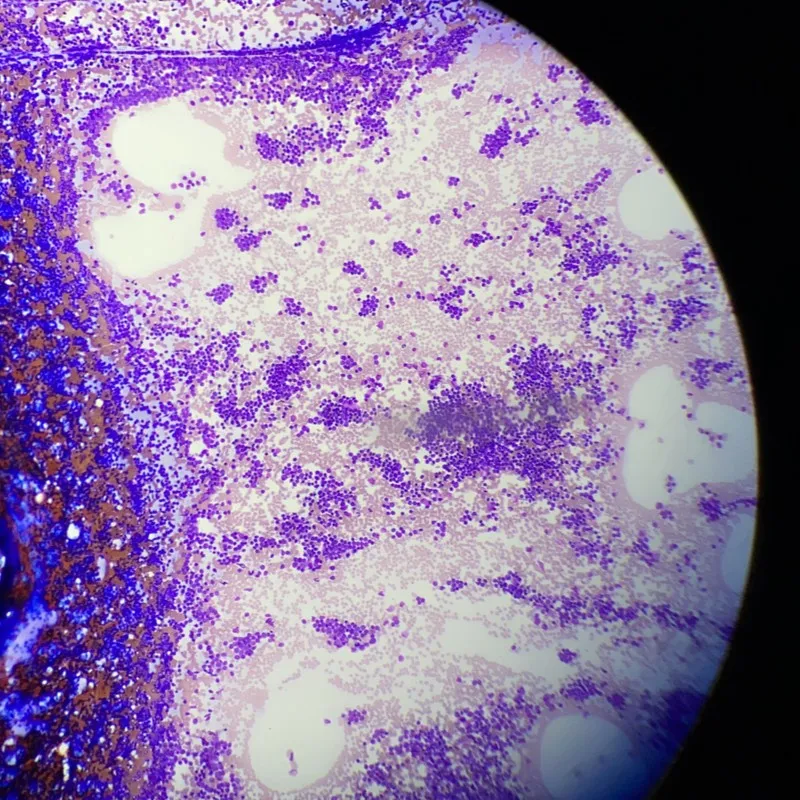

MRD (Minimal Residual Disease) is one of the strongest predictors of outcomes in blood cancers, including myeloma. While new treatments today are helping myeloma patients achieve complete responses, a small number of cancer cells can remain in your body and may cause your myeloma to return. Using highly sensitive tests like the clonoSEQ MRD tests to test results what cancer cells, if any, remain in your body after achieving a complete response is needed in order to asses therapy responses over time and be aware of what your myeloma status truly is.